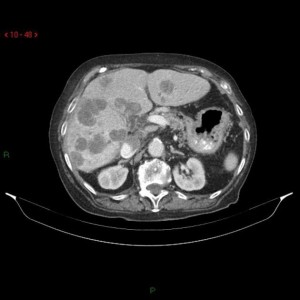

Συνήθως οι ασθενείς αυτοί είναι ασυμπτωματικοί. Συμπτώματα όπως κοιλιακό άλγος και απώλεια βάρους σχετίζονται με προχωρημένη ηπατική νόσο και κακή πρόγνωση. Ο προεγχειρητικός απεικονιστικός έλεγχος περιλαμβάνει ελικοειδή αξονική τομογραφία κοιλίας και θώρακος, μαγνητική τομογραφία κοιλίας όταν υπάρχει αμφιβολία για τη φύση των ηπατικών εστιών καθώς και αγγειογραφία ήπατος σε επιλεγμένες περιπτώσεις. Η τομογραφία εκπομπής ποζιτρονίων (PET scan) είναι περισσότερο χρήσιμη για την ανίχνευση εξωηπατικών μεταστάσεων.

Αξονική τομογραφία κοιλίας: Πολλαπλές ηπατικές μεταστάσεις